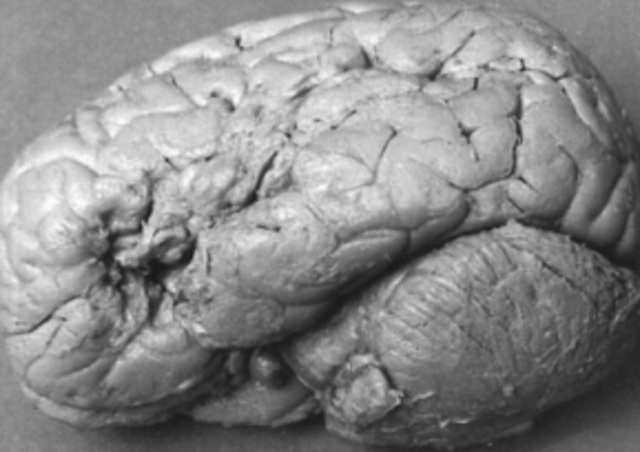

Hizo la primera correlacion específica entre una facultad psicológica compleja (el lenguaje) y una localización precisa en el cerebro (circunvolución frontal) estudiando, post mortem, el cerebro del "paciente TAN"

Al examinar este cerebro se determinó que la lesión no se encontraba en la tercera circunvolución frontal (como en el caso del paciente tan) sino en la primera circunvolución temporal.